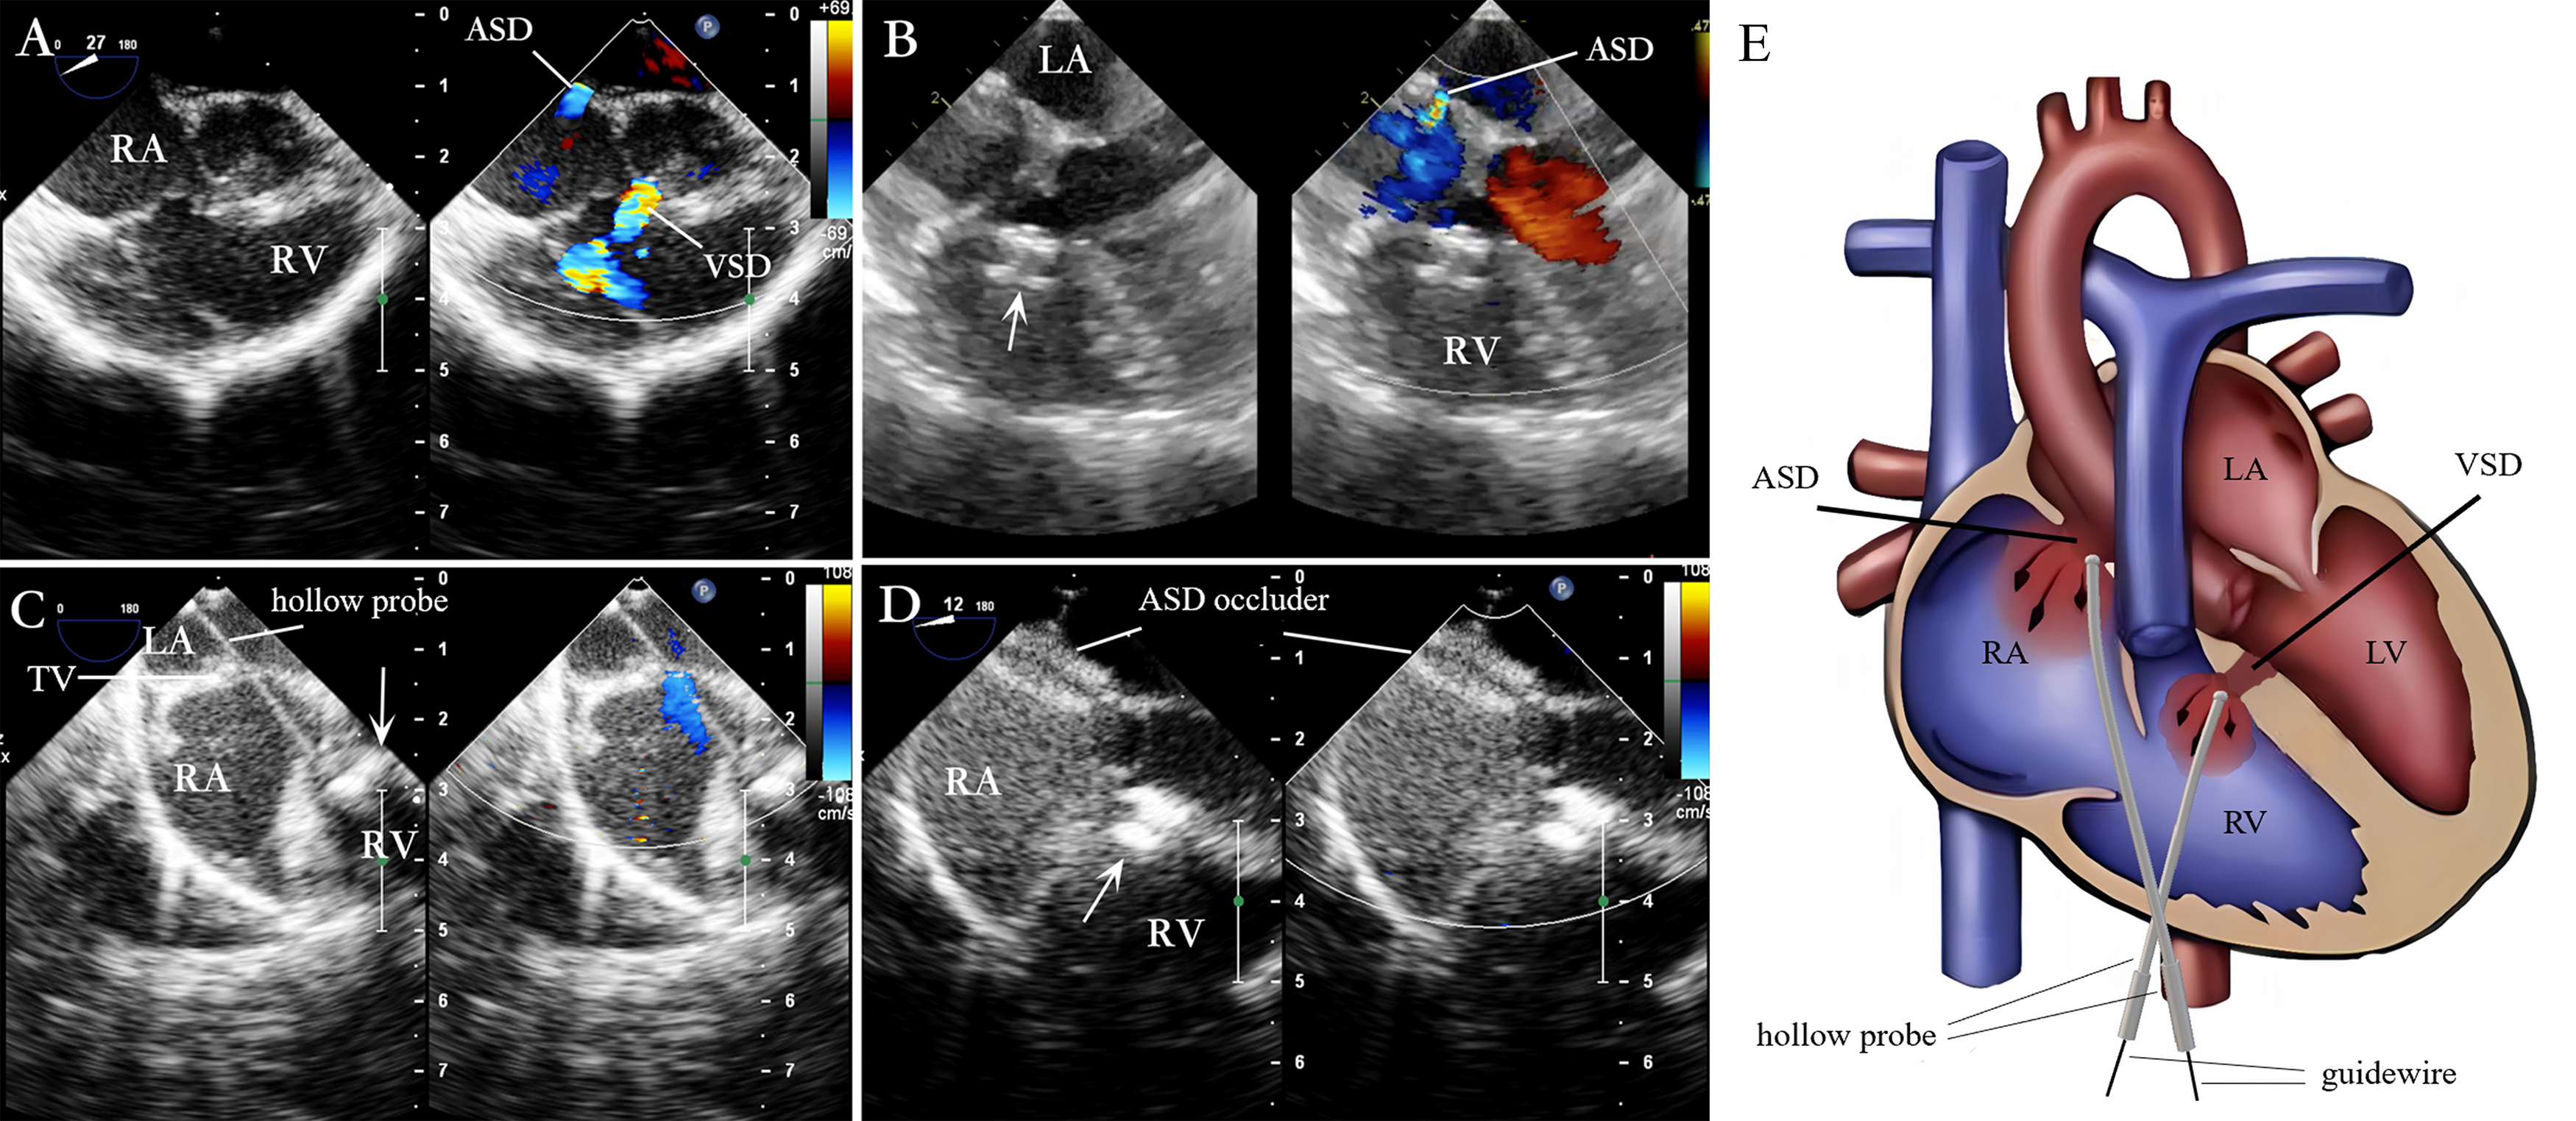

The selected device, connected with a “safety wire” (4-0 or 5-0 polypropylene stay suture), was screwed onto the delivery cable and retracted into the loading sheath. A 1.5 to 3 cm parasternal incision was made in the fourth right intercostal space (within the “bikini lines” in female patients). Superficial tissues were dissected bluntly to enter the pleural space. The pericardium was incised and cradled. Two parallel purse-string sutures of 4-0 or 5-0 polypropylene were placed on the right atrium near the atrioventricular groove. Heparin was administered at a dose of 100 IU/kg. The VSD occluder was then delivered using the PADS. First, the right atrial purse string suture was punctured, and a Z-shaped hollow probe was inserted into the right atrium. Under TEE guidance, the probe tip was advanced through the tricuspid valve into the right ventricle, and the direction of the probe tip was adjusted towards the VSD opening on the right ventricular side (Fig. 3A). Then, a straight, short guide wire was inserted through the probe’s outer hole and across the VSD before the probe was withdrawn. Subsequently, a delivery sheath was introduced along the short guide wire to position it within the left ventricle. The VSD occluder was advanced to the left ventricle, and the left and right disks were deployed sequentially on the respective ventricular sides. Under TEE observation, the position of the occluder was tested repeatedly by pushing and pulling. Once satisfied with its position, shape, and impact on surrounding tissues, the occluder was released. The safety wire was maintained for 5–10 minutes, and a pharmacological blood pressure test (raising systolic pressure to 150 mmHg for adults and 130 mmHg for children) was performed. If satisfied, the safety wire was removed.

Fig. 3. Schematic of the peratrial approach. (A) The Z-shaped hollow probe is directed towards the VSD through the TV. (B) First, the Z-shaped hollow probe is directed through the RA, TV, and RV toward the VSD to complete the VSD occlusion. Then, through the same right atrial puncture site, the hollow probe is used to complete the ASD occlusion. Note: RA, right atrium; RV, right ventricle; LA, left atrium; LV, left ventricle; TV, tricuspid valve.

After VSD closure, ASD occlusion was performed through the same atrial puncture site. The delivery sheath containing the ASD occluder was inserted through the right atrial purse. The direction of the delivery catheter was adjusted to cross the ASD and enter the left atrium (Fig. 3B). Then, the ASD was occluded. This process does not require a guide wire, and the imaging of the delivery sheath remains clear. Repeated push–pull tests were performed to check the stability of the ASD occluder, residual shunt (RS), and potential impact on the mitral valve and coronary sinus. Once satisfied, the occluder was released.

Under TEE guidance for evaluating VSD and ASD (Fig. 4A), a guidewire, delivery sheath, or hollow probe was used to pass through the VSD. Then, the VSD occlusion was completed (Fig. 4B). Then, the delivery catheter was adjusted, or the hollow probe was re-inserted gently. Next, it was cautiously advanced through the tricuspid valve as it opened to avoid damaging the valve (Fig. 4C). The delivery catheter was passed through the ASD to enter the left atrium before a guidewire was inserted to pass through the ASD into the left atrium; the ASD delivery system was advanced along this guidewire. The occluder was placed to complete the occlusion (Fig. 4D). The position and morphology of the ASD occluder, the RS, and the regurgitation of adjacent valves were evaluated. Once the TEE confirmed the position of the ASD occluder to be satisfactory, the delivery system was removed. The schematic diagram of the procedure is shown in Fig. 4E.

Fig. 4. Lower mini-sternotomy perventricular approach for simultaneous occlusion of VSD combined with ASD. (A) VSD combined with ASD. (B) After puncturing the RV wall and occluding the VSD, the four-chamber heart view illustrates the ASD. (C) After occluding the VSD, the straight hollow probe passes from the RV through the TV to the RA and is adjusted to pass through the ASD. (D) A guidewire and delivery sheath are inserted along the probe hole to complete the ASD occlusion. (E) The hollow probe is directed towards or through the VSD via the RV puncture site for VSD occlusion. Then, through the same right ventricular puncture site, the hollow probe is directed through the TV into the RA, towards or through the ASD, for ASD occlusion. Note: arrow = VSD occluder.